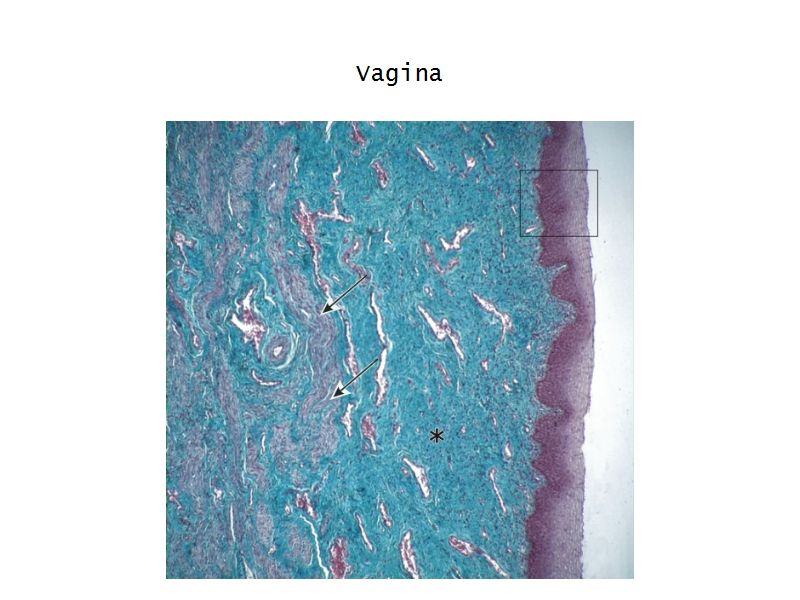

Vagina

- Fibromuscular tube with 3 layers

- Inner mucosa

- Middle muscle layer

- External adventitia

Mucosa

- Epithelium

- Thick stratified squamous nonkeratinized

- Lamina propria

- Fibroelastic connective tissue

- Rich in elastic fibres

- Contains lymphoid elements

- Deep portion highly vascular

- No glands

Muscle layer

- Thin inner circular

- Thick outer longitudinal

- External orifice ring of skeletal muscle

Adventitia

- Fibroelastic connective tissue

- Fixes onto surrounding structure

- Blood vessels and nerves